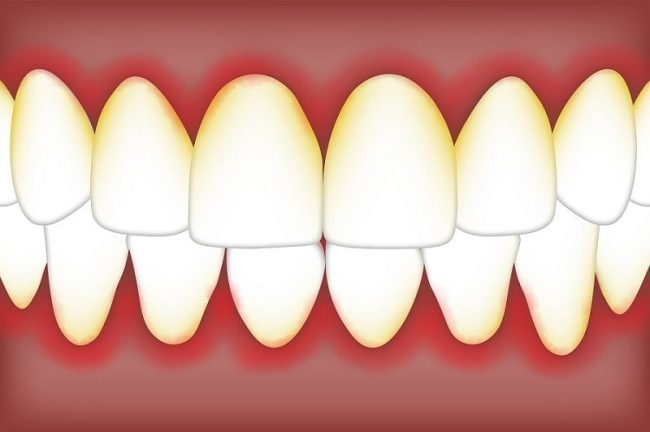

What is Periodontitis? Periodontitis, otherwise known as gum disease, is a serious bacterial infection of the gums. It is caused by bacteria and ranges in severity. Over time, periodontitis can lead to damage of the soft tissue, teeth, and bones, possibly resulting in the loss of teeth. This condition is treatable, and with care,…